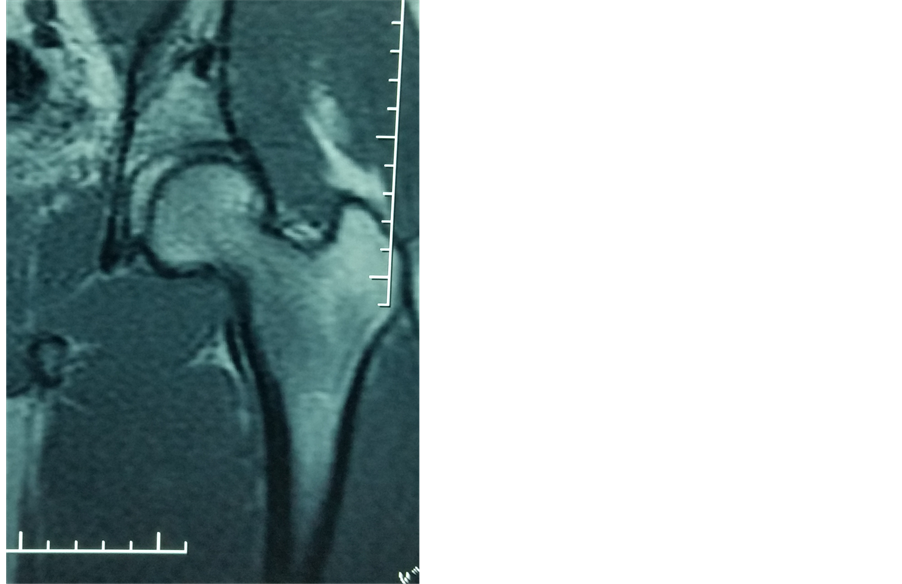

Mr. DS was 31 with no medical history, when he was referred to us the 06/09/2013; for a left hip injury following a road traffic accident. On September 6th 2013, the patient was riding a motorbike when he collided with another motorbike rider, hitting the left knee. On admission, clinical examination revealed abduction, external rotation and flexion at the hip to the same limb. Plain X-rays showed obturator dislocation of the hip (Figure 7). Treatment consisted of closed reduction the next day, followed by 15 days of bed traction. A control MRI 20 months post-traumatic showed no signs of avascular necrosis of the femoral head (Figure 8).

Figure 8. MRI showing no signs of avascular necrosis of the femoral head (patient 4).